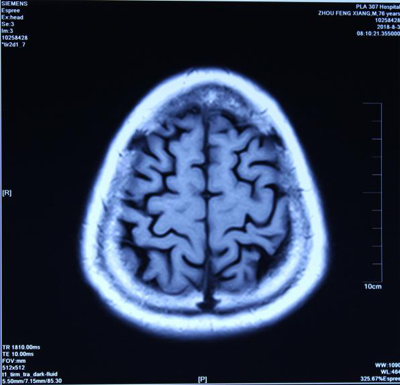

报告单1(治疗前) 报告单2(治疗后) 报告单1是孙先生治疗前, 2014年9月23日进行核磁共振(MRI)检查报告中检查所见:“幕下小脑、脑干亦萎缩明显”。报告单2是孙先生治疗后: 2014年11月29日用纯中药治疗2个月后,进行核磁共振(MRI)检查报告中检查所见:“幕下小脑未见异常信号”。临床症状明显消失。 典型病例二(影像比较):脑细胞再生长使脑组织增长 患者:周先生 男 76岁 退休干部,治疗前面无表情、意识不清,不能自己活动等。做核磁共振检查进行治疗前后比较如下:

图1-1 (治疗前) 图1-2(治疗前)

图1-3 (治疗后) 图1-4(治疗后) 上图是严重脑萎缩用中药治疗半年核磁共振影像的前后对比:周先生 男 76岁 面无表情,意识不清,记忆严重减退二年余,肢体活动困难,病情渐渐加重,对自己名字不知道,自己吃的什么饭不清楚,不能自己行走等病情,临床诊断为:阿尔茨海默病(老年痴呆症),脑中风后遗症。2018-年02月06日磁共振影像显示:脑萎缩(图1-1、图1-2下端黑洞脑组织严重缺损)。经中药治疗半年,患者面部病情正常,意识恢复正常,对自己的名字及他人都清楚,吃过的食物过后也记得,能够与他人正常交流,能够自己行走活动。2018年8月3日核磁共振影像(图1-3、图1-4)显示:脑萎缩与2018年2月6日(图1-1、图1-2)比较脑萎缩明显恢复(脑组织严重黑洞缺损消失)。影像证明了:经治疗使的脑细胞再增长,使脑组织增多,使脑组织逆生长。 我们编著了《大脑复原理论 大脑细微结构修复术》(成了脑科研究的参考资料)以及近期编著了《大脑复原理论 大脑医疗技术探秘》,介绍了脑细胞再生长的原理和临床治疗成功的验证,是我们中国人在国际上首先提出了脑细胞再生长和成功做到了脑细胞再生长!我们对大脑萎缩、小脑萎缩、脑科疑难疾病的有效治疗,是用核磁共振进行治疗前后的对比。 2016年6月在中国海南博鳌召开的“2016世界医疗旅游和世界健康学术大会”和2016年7月在曼谷召开的“世界传统医学大会”上,贾学铭教授发表并介绍用纯中药使脑细胞再生长治疗脑萎缩、阿尔茨海默(老年痴呆症)能够治愈的效果,用核磁共振影像片子进行治疗前后的对比,证明脑组织有了新的增多,做到了使脑细胞再生长的效果,改变了过去医学界不可治愈的理论,受到了美国、德国、澳大利亚、意大利、英国、法国等参会的代表和许多国家专家的认可和赞扬。这个“脑细胞能够再生长”的理论,到目前是贾学铭教授和贾沅潽医学博士首先提出的,也是首先用影像证明能够做到的,为人类健康事业流出一定的贡献。 在党的十八大以来,为强我中华,创新中医、发展中医,创新做到了用中医中药的方法,艰难的创新再创新的实践,做到了脑细胞再生长、脑组织能够再生长,造福了脑科疑难病患者,脑细胞再生长,治疗了大量的脑萎缩病人。对脑科医学理论和脑科疑难病治疗有重要的参考意义。在国际上产生了很好的影响,显示了中国中医药的魁宝,2016年7月在曼谷召开的世界传统医学大会上获得了《世界传统医学突出贡献奖》和《世界传统医学终身成就奖》。对现在及往后的脑科研究和脑科疑难病的治疗有重要的意义,为国际脑科医学的研究和治疗做出了显著的贡献。 贾学铭教授,贾沅潽博士介绍: 贾学铭,字:瀚珺,教授, 主任医师,从事中医工作50年,资深中医专家,中医脑科专家,中国传统医学名医,中国名人俱乐部副主席兼健康委员会主任,中华中医药学会专家委员,英国中医师学会知名专家、中医顾问,中国生命关怀协会心脑血管病防治指导专家,山东潍坊吉缘堂抗衰老中医药研究所法人等职。北京同仁堂中医医院贵宾楼专家,北京同仁堂王府井中医院心脑血管病专家,301医院远程医学中心专家,301健康管家心脑血管病专家,北京八大处中西医结合医院脑科专家。 贾沅潽医学博士,国外留学10年,2012年回国,山东潍坊吉缘堂抗衰老中医药研究所所长等职。通过我们研究治疗的临床案例等研究,2015年编著了《大脑复原理论 大脑细微结构修复术》,2019年编著了《大脑复原理论 大脑医疗技术探秘》,介绍了脑细胞再生长的原理和治疗的成功验证,是我们中国人在国际上首先提出了脑细胞再生长和成功做到了脑细胞再生长!为脑科医学作出了非常有意义的贡献! |